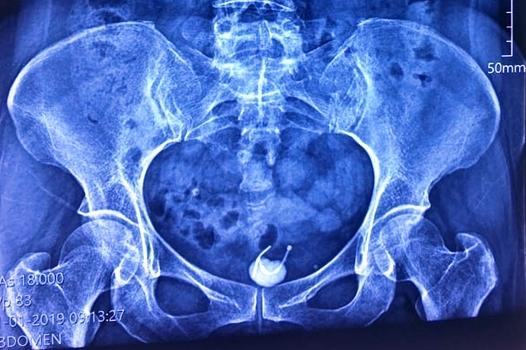

Ảnh chụp X-quang cho thấy vòng tránh thai bị mắc kẹt ở bàng quang người phụ nữ. Ảnh: BSCC

Bệnh nhân là bà T.T.H, 54 tuổi, ngụ Đồng Nai nhập viện trong tình trạng đau bụng vùng hạ vị kèm tiểu khó. Qua thăm khám kết hợp với kết quả siêu âm, bác sĩ phát hiện bệnh nhân có dị vật hình chữ T qua thành bàng quang và có sỏi bàng quang.

Bác sĩ Phan Văn Ở, Phó Giám đốc bệnh viện cho biết dị vật là chiếc vòng tránh thai hình chữ T. Chiếc vòng này theo như bệnh nhân kể thì đã được đặt từ 31 năm trước, song bị rơi khỏi vị trí cố định ban đầu, chiếc vòng đi xuyên thành bàng quang và tạo sỏi làm chị H. đau bụng và tiểu khó.